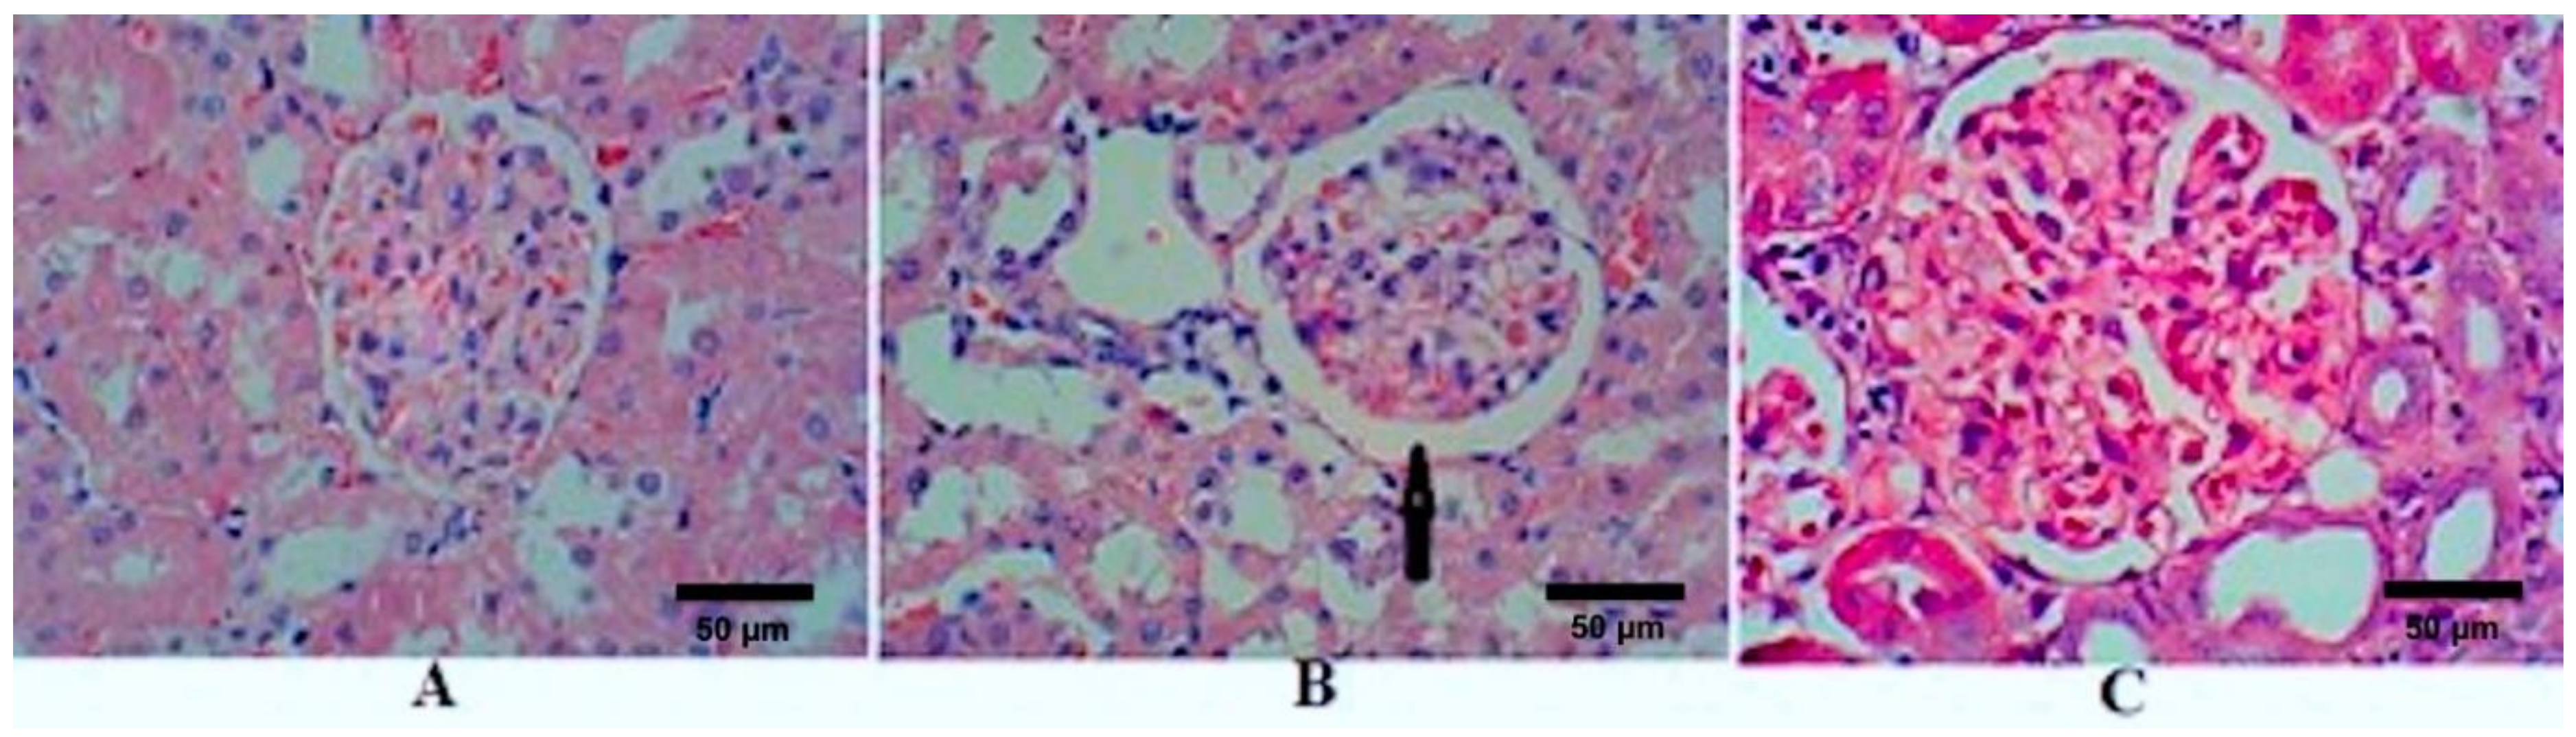

| Diameter of RC (µm) | 193.48 ± 20.12 | 228.08 ± 23.42 * | 216.95 ± 11.56 | 3.44 | 0.077 |

| Diameter GM (µm) | 158.10 ± 19.98 | 170.00 ± 22.81 | 184.40 ± 6.92 | 2.15 | 0.172 |

| Diameter of BS (µm) | 22.10 ± 4.29 | 30.93 ± 4.96 * | 16.23 ± 1.71 # | 14.33 | 0.002 |

| Arteriolosclerosis | Grade 0 | Grade 3 | Grade 1 | ||

| Inflammatory cell infiltration | Insignificant | Mild | Mild | ||

| Hyaline droplets | Insignificant | 30% | 20% |